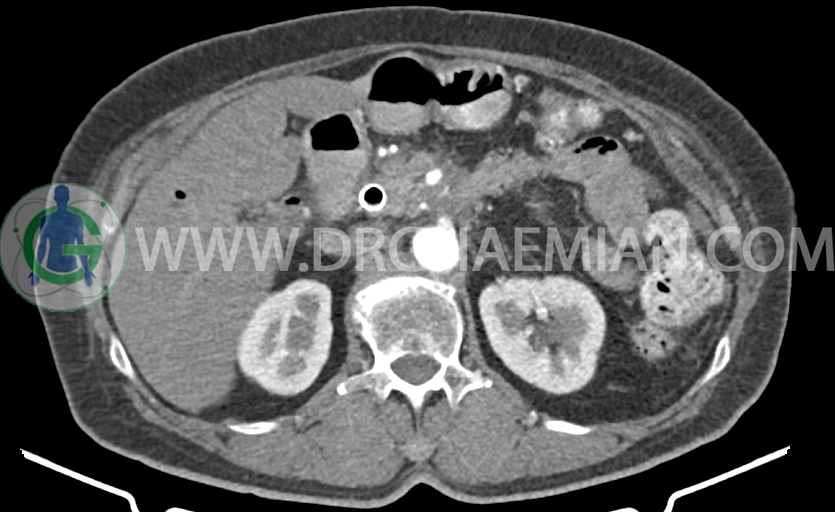

در سی تی اسکن اسپیرال شکم و لگن با و بدون کنتراست خوراکی و وریدی- پروتکل پانکراس (مولتی دیدکتور 16 با مقاطع ظریف و بازسازی های ساژیتال و کرونال) :

– توده هیپودنس ill – defined با حداکثر دیامتر تقریبی 50mm در ناحیه گردن و پروگزیمال body پانکراس( بدون تغییر قابل توجه در سایز نسبت به سی تی اسکن 1401/9/17 )

همراه با encasement در SMA ،SMV، شریان اسپلنیک، شریان هپاتیک و پروگزیمال ورید پورت (بدون تغییر نسبت به سی تی اسکن 1401/9/17)

– اتروفی دیستال پانکراس (بدون تغییر نسبت به سی تی اسکن 1401/9/17)

– لنف نودهای متعدد با حداکثر SAD=6mm در اطراف توده فوق الذکر، پانکراس و مزانتر (بدون تغییر قابل توجه نسبت به سی تی اسکن 1401/9/17)

-Fat stranding در اطراف پانکراس و فضاهای مزانتر در Mid line و Mid abdomen

– Fullness در سیستم پیلوکالیسیل کلیه ها (بیشتر سمت چپ) احتمالاً فاقد اهمیت بالینی است و نسبت به سی تی اسکن قبلی بهبود نشان می دهد.